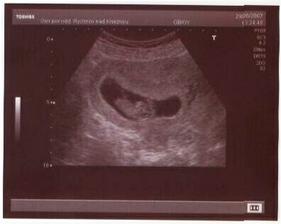

V lednu 2007 vysazena HA, v květnu se to podařilo, v červnu jsme se vzali a ted se moc těšíme na leden 2008.